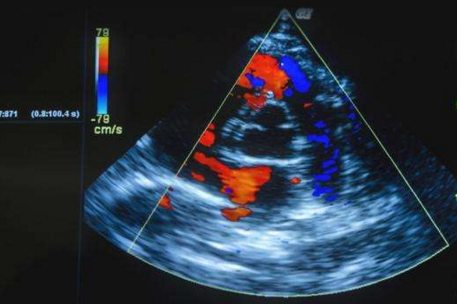

心臟彩超檢查工作原理是多普勒效應(yīng),集各種超聲診斷為一體,將心臟血流描繪得微妙微肖,是較好的超聲診斷設(shè)備。常用于診斷先天性心臟病,與心電圖、胸部X線檢查一樣,是心臟病檢查的常規(guī)檢查手段之一。

(1)能同時(shí)顯示心腔某一斷面上異常血流的分布情況。

(2)可以明確血流的性質(zhì)是層流、湍流還是渦流。

(3)可以測(cè)量血流束的面積、輪廓、長(zhǎng)度、寬度。

(4)能反映血流的途徑及去向。

(5)血流信息能顯示在二維(扇型或B型)切面圖上,或能顯示在一維(M型)圖上,更直觀地反映了心臟結(jié)構(gòu)異常與心臟血流動(dòng)力學(xué)異常的關(guān)系。